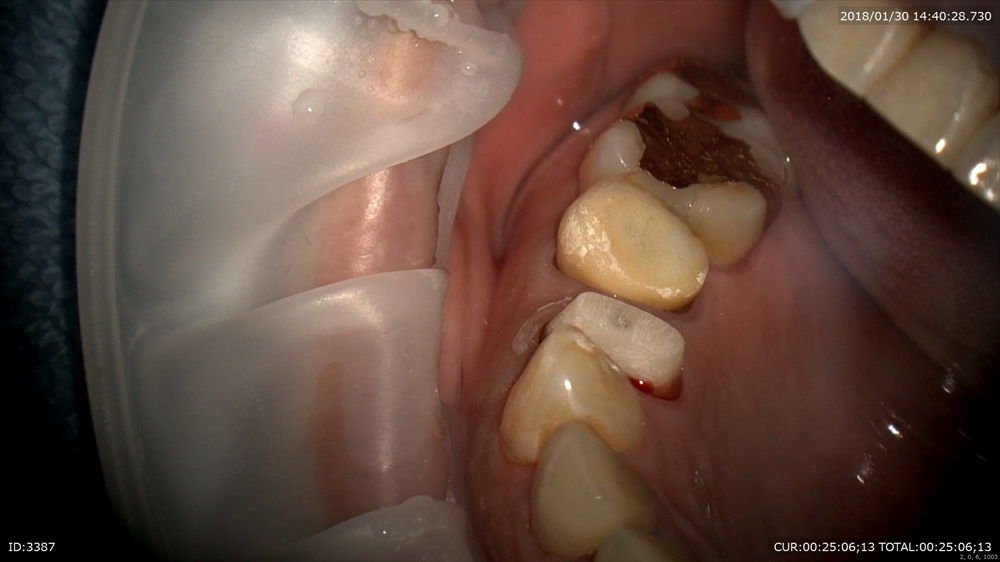

この方他院で治療後再発。膿が歯茎からでてきました。

今日 腫れ、膿、違和感が消え絶好調!!